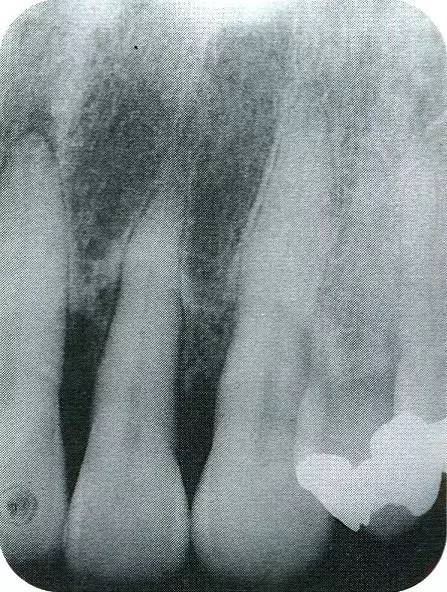

640.webp (6).jpg

▲圖7-7  術(shù)前,術(shù)后的x片。確認出現(xiàn)骨再生,牙槽嵴硬線。